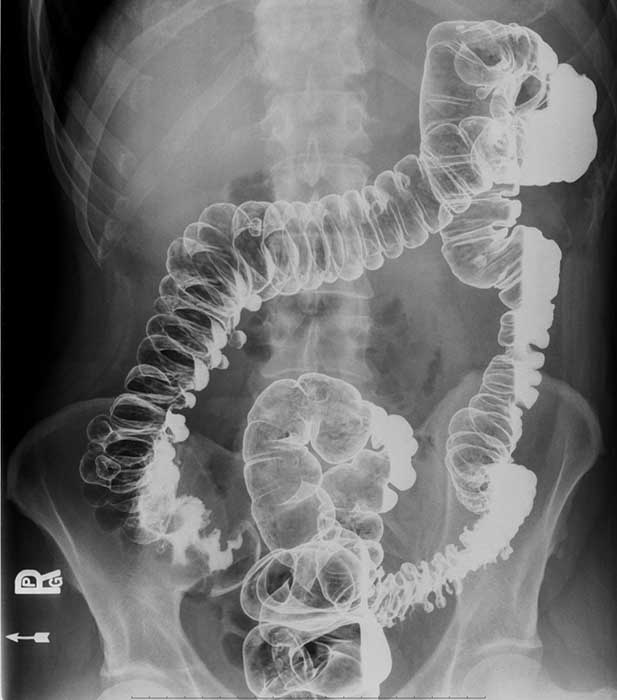

Where does volvulus most commonly occur?

In the cecum and sigmoid colon. (image shows cecal volvulvus)

How does cecal volvulus occur?

The cecum twists on its long axis and often displaces upward and to the left.

How does sigmoid volvulus occur?

The sigmoid twists on its mesenteric axis, rotating left or right.